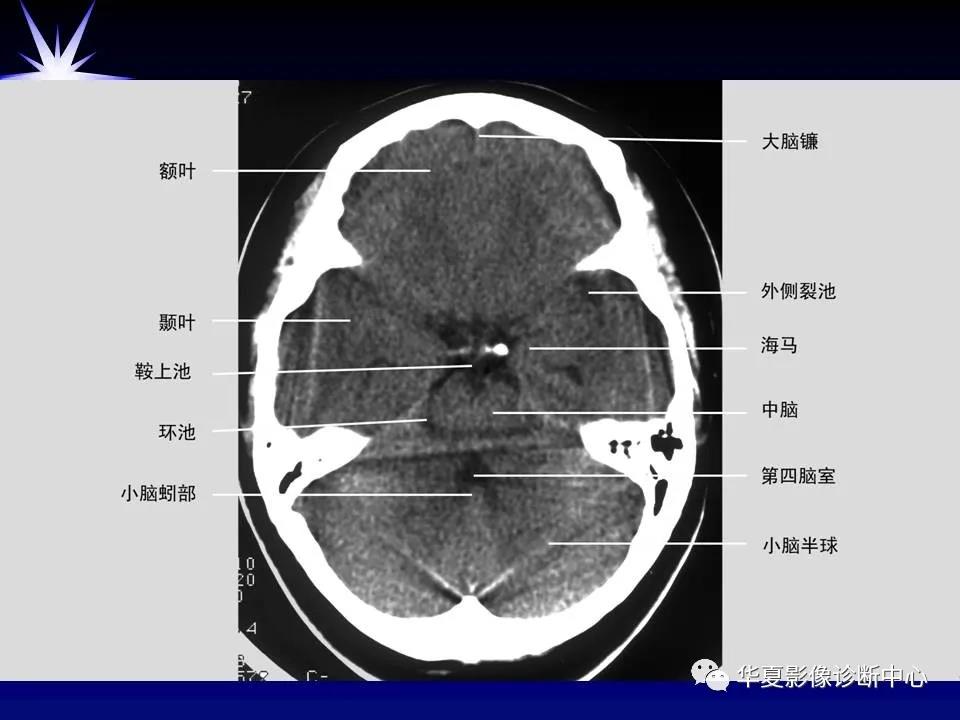

来源:华夏影像诊断中心